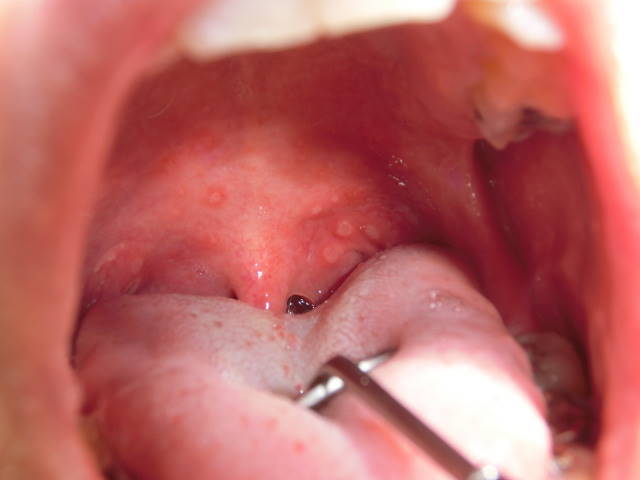

その後、咽頭粘膜が赤くなり、口腔に1-5mmの小水疱が数個出現します。

小水疱が破れて潰瘍になると痛みます。